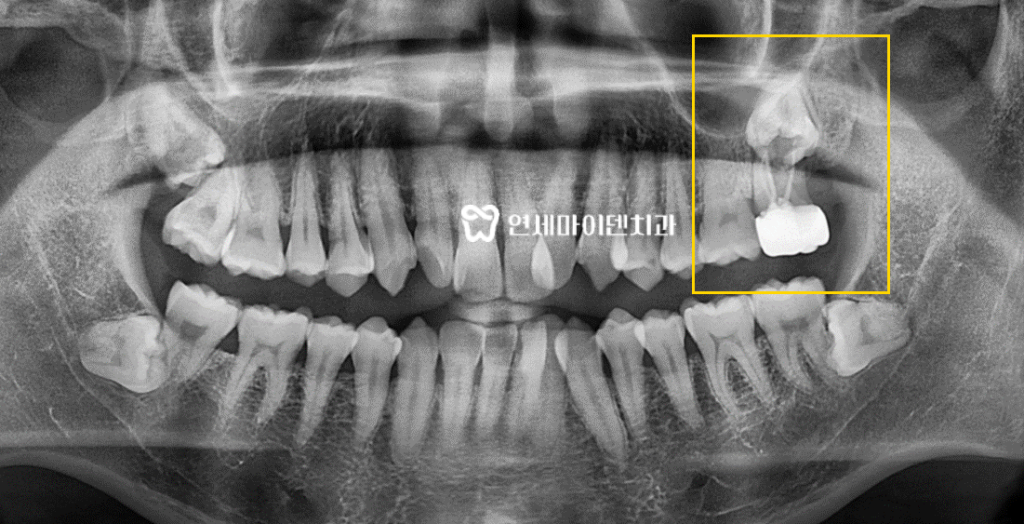

엑스레이 상으로 확인해보니

어금니 바로 아래에 매복 사랑니가 있는 것이 보입니다.보통 사랑니는 잇몸 끝쪽에 있지만

이 환자분의 사랑니는 어금니 바로 아래에서 염증을 유발하고 있었습니다.

특히 엑스레이상 까맣게 보이는 염증으로

잇몸 뼈가 이미 많이 녹아있는 상태였습니다.고난이도 치료를 많이 시행하고 있는 저희 연세마이덴치과지만

발치 후 임플란트도 쉽지 않아보이는 상황이었습니다.하지만 발치 후 임플란트 없이 치아를 놔둔다면

잇몸도 내려앉고 다른 치아에도 안 좋은 영향을 줄 수 있기때문에최대한 임플란트가 가능하도록 세밀한 치료 계획을 세웠습니다.

CT 촬영 후 3D 네비게이션을 통해 3차원적으로

임플란트를 식립할 최적의 위치와 크기, 깊이를 설정해주었습니다.정밀하게 식립 위치를 계산하고 최적의 깊이까지 임플란트를 넣어주는 것이

임플란트 성공률을 높이는 중요한 준비단계입니다.

아직 이식된 뼈가 단단하게 성숙되지는 않은 상태이기 때문에

회복되는 경과를 지켜보면서 뼈가 자리를 잡으면 최종 보철물을 올려드릴 예정입니다.매복 사랑니 발치와 임플란트

엑스레이에서도 보이듯이 시간이 지나면서 까맣게 녹아있던 뼈 부분이

하얗게 재생되는 걸 확인할 수 있습니다.임플란트를 해야하는데 어려운 상황에 있어 고민이신 분들께